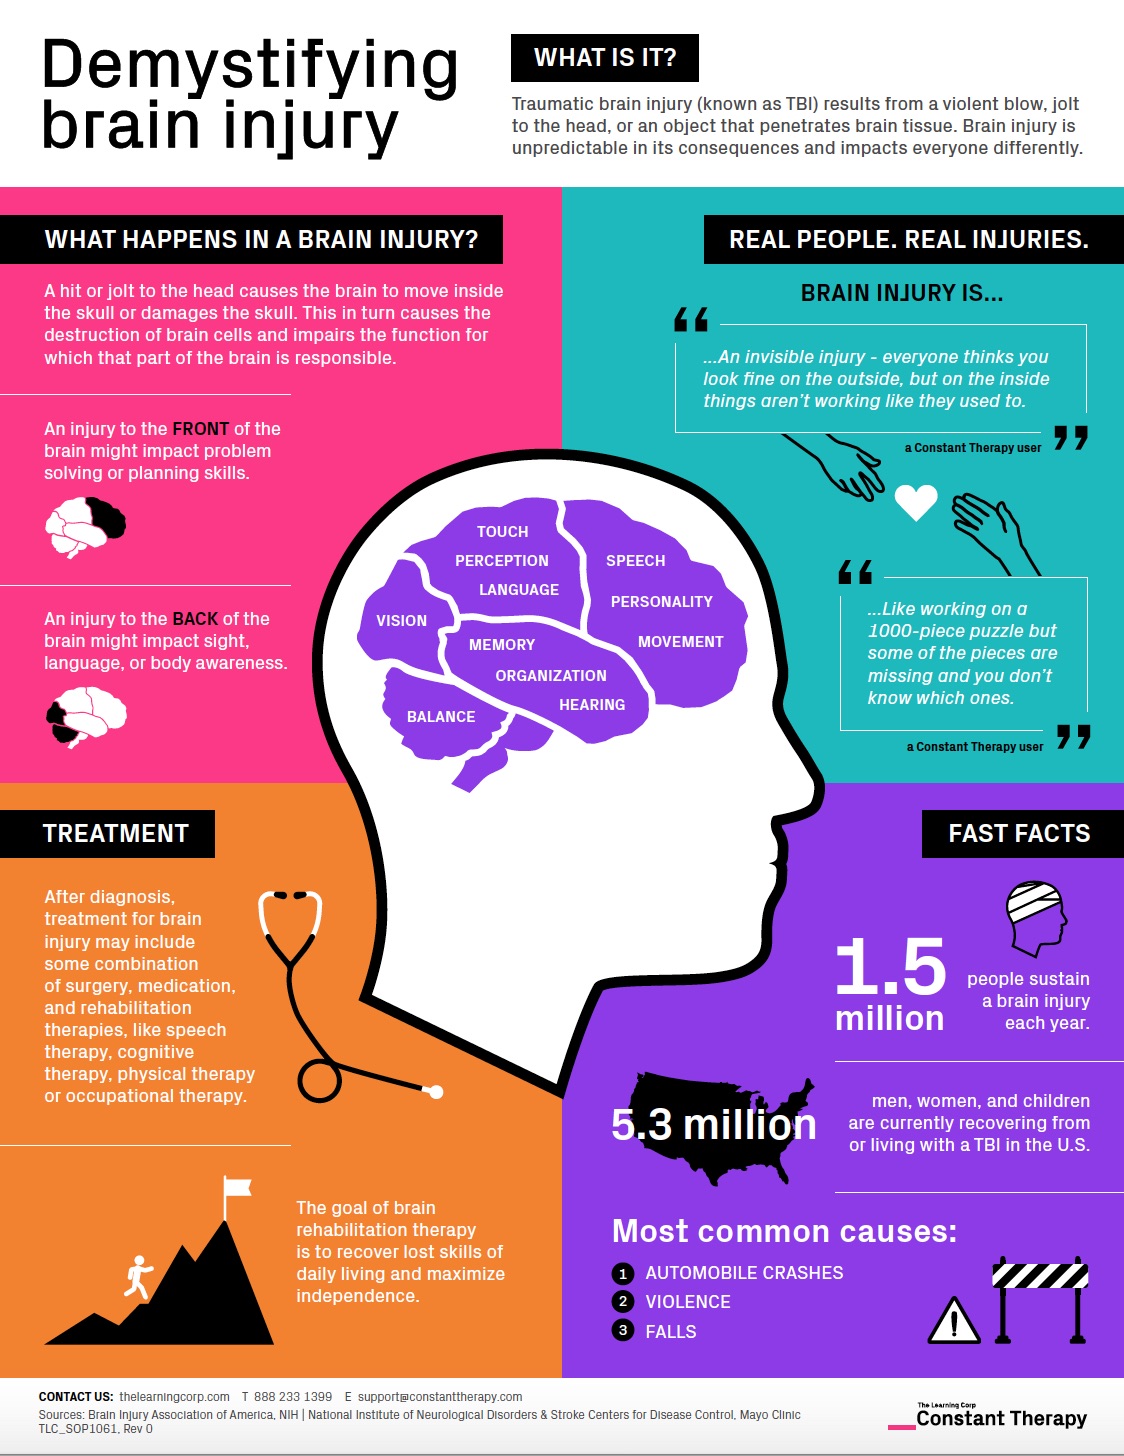

Demystifying Brain Injury Infographic Explains The Basics Constant

https://thelearningcorp.com/wp-content/uploads/2019/03/DemystifyingBrainInjury.jpg